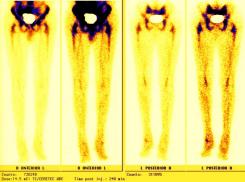

Nuclear Scan Images of Lower Torso & Lower Legs

These images were captured in order to determine why Liam’s bones broke so easily playing a video game and to also determine if there

was any Osteomyelitis. This is the diagnosis report from the scan. "There is mild increased activity noted in the lateral side of the left

ankle. However the patient does have a cast on the left leg. This uptake can be secondary to either inflammatory or infectious change within

either the skin or adjacent bone." Various contrast were used to enhance image details. The last images reminds one of the Shroud of Turin.

Hummm, makes one wonder... ;-)